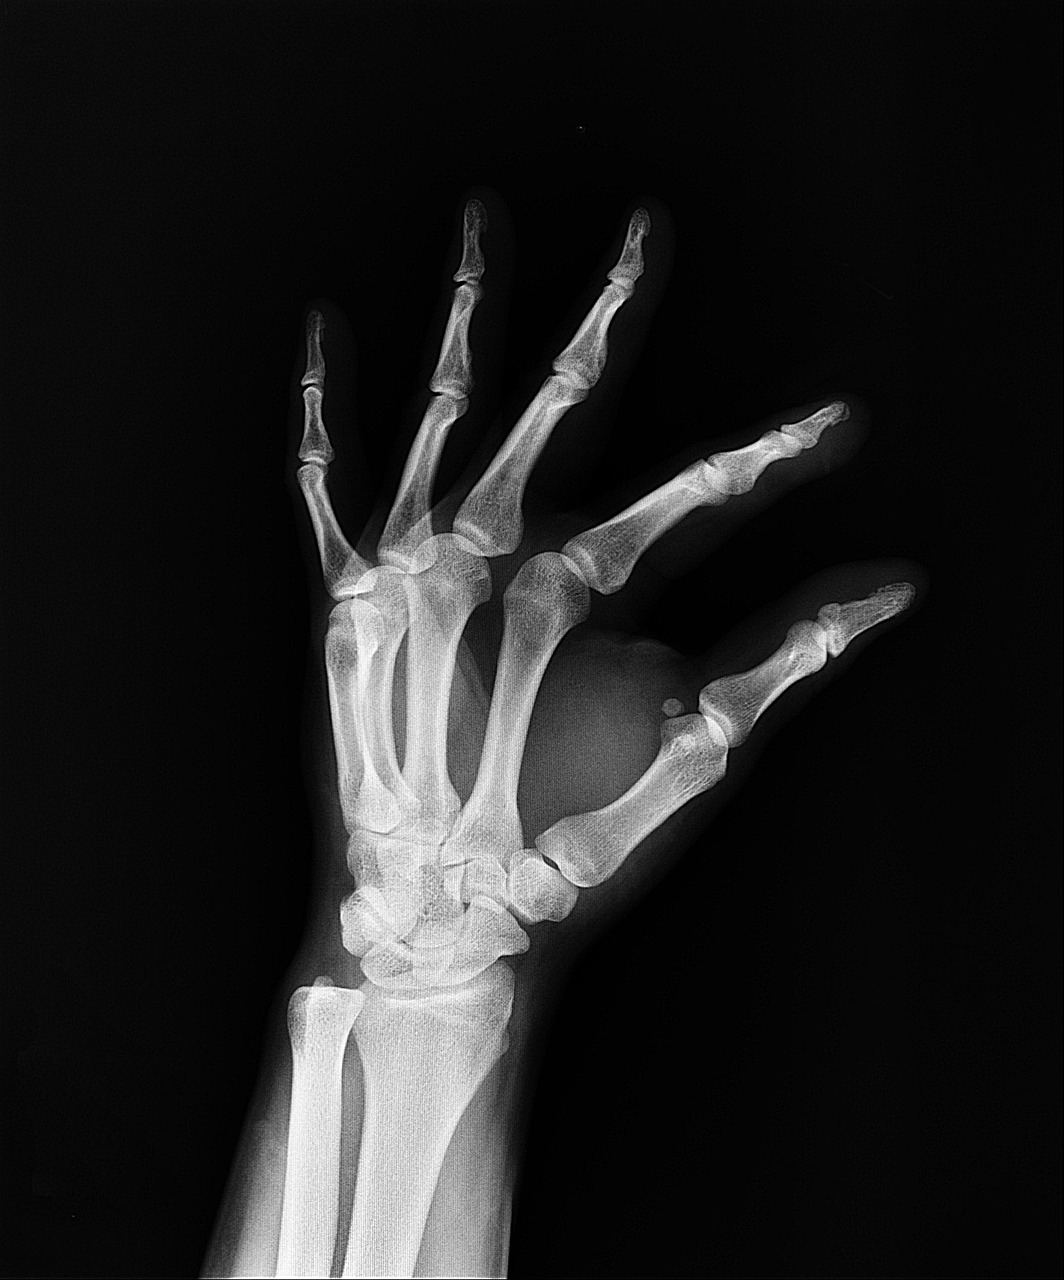

Ein zentraler Bereich, in dem künstliche Intelligenz einen bisher unerreichten Einfluss auf Diagnoseverfahren hat, ist die medizinische Bildgebung. Traditionell basieren radiologische Diagnosen auf der Verarbeitung von Röntgenaufnahmen, Computertomographie (CT) oder Magnetresonanztomographie (MRT) durch erfahrene Radiologen. Heute unterstützen KI-Algorithmen diese Fachärzte durch automatisierte Mustererkennung und quantitative Auswertung, wodurch die Diagnosen nicht nur schneller, sondern auch präziser werden.

Siemens Healthineers ist ein Vorreiter bei der Entwicklung solcher KI-gestützten Systeme. Zum Beispiel ermöglicht ihre Technologie, Anomalien wie Verkalkungen der Herzgefäße oder Läsionen bei Krebserkrankungen in frühen Stadien zu erkennen. Die Bildqualität wird durch KI-gestützte Bildrekonstruktion verbessert, sodass Untersuchungszeiten drastisch verkürzt werden können. So dauert eine Knie-MRT-Untersuchung inzwischen nur noch etwa zwei statt zehn Minuten.

- Erhöhung der Diagnosegenauigkeit: KI kann feine Veränderungen im Gewebe erkennen, die menschlichen Augen entgehen könnten.

KI-Systeme analysieren große Mengen medizinischer Daten und erkennen Muster, die für den Menschen schwer zu identifizieren sind. Dies führt zu präziseren und schnelleren Diagnosen, z. B. bei Bildanalysen wie Röntgen oder MRT.